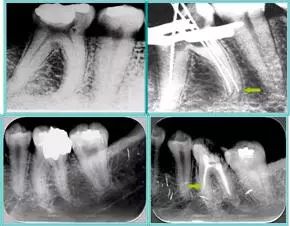

牙胶尖什么颜色【根管治疗】根管治疗的细节把握_https://www.jmylbn.com_新闻资讯_第19张

( 1 )干髓。

干髓治疗时,开髓后髓腔里注入甲醛甲酚 FC 灌髓,三聚甲醛固定,髓室底放置三聚甲醛缓慢释放,进行根管无害化处理。髓腔缓慢坏死,机体代偿出现根管钙化。如果患者在封闭腔出现出现病变,由于髓腔钙化,根管堵塞严重,检查治疗比较困难。

解决方法:1 )彻底去除坏死的牙髓组织。2 )借助化学性药剂,如 EDTA 等。3 )初锉选用8#或10#K 锉,平衡力法探察到工作长度 , H锉上下提拉法使根管扩大,提高工作效率。

牙胶尖什么颜色【根管治疗】根管治疗的细节把握_https://www.jmylbn.com_新闻资讯_第20张

左图和上图为干髓治疗后牙齿,龋齿疏通后进行根管充填。

( 2 )塑化。

传统的治疗思维:塑化治疗后患者需将塑化液清理干净,达到彻底根管治疗目的。牙胶尖什么颜色【根管治疗】根管治疗的细节把握_https://www.jmylbn.com_新闻资讯_第21张

目前的治疗思维:以前塑化治疗效果好时不必清理干净塑化液。对于根尖没有病变的患者,可借助溶解剂建立通路;根尖存在病变的患者往往是塑化治疗不理想患者,需要彻底打通通路。